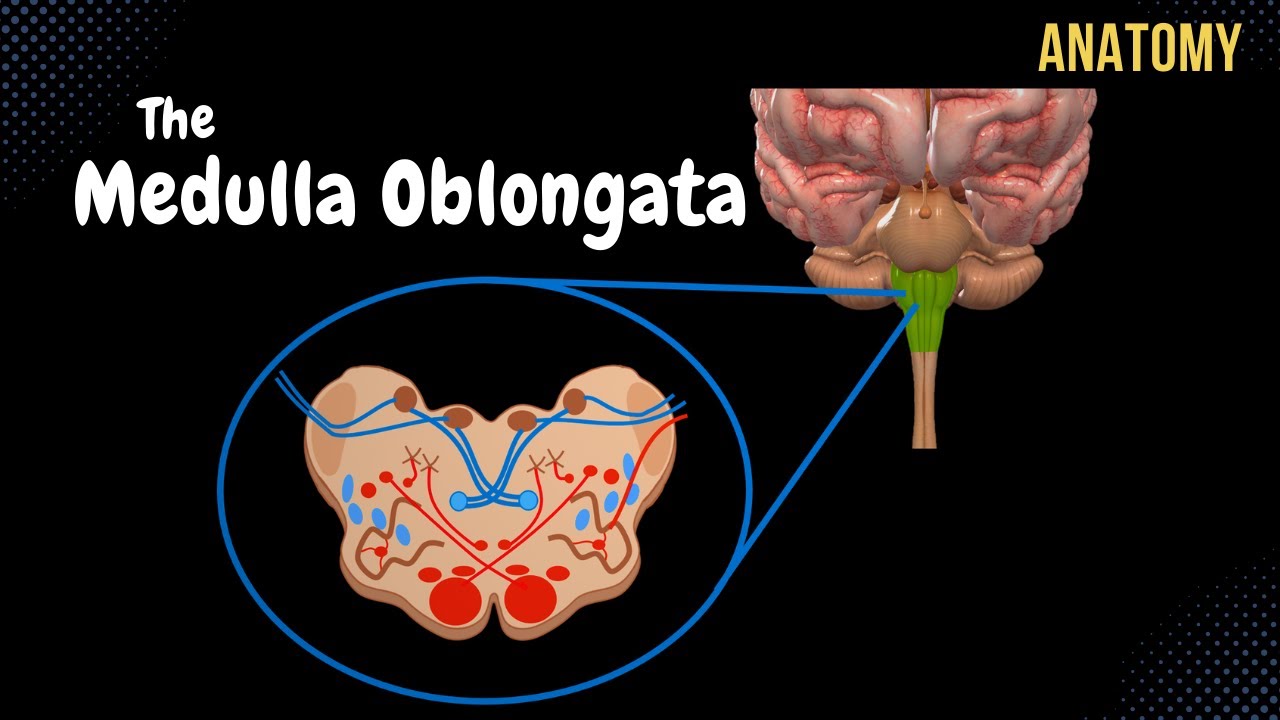

The Medulla Oblongata - Internal Structure - Vasculature

![Figure, Medulla oblongata] - StatPearls - NCBI Bookshelf](https://www.ncbi.nlm.nih.gov/books/NBK551589/bin/Medulla__oblongata.jpg)

Figure, Medulla oblongata] - StatPearls - NCBI Bookshelf

Olives of Medulla - AnatomyZone

Brain Anatomy Medulla Oblongata And Spinal Cord Cross Section